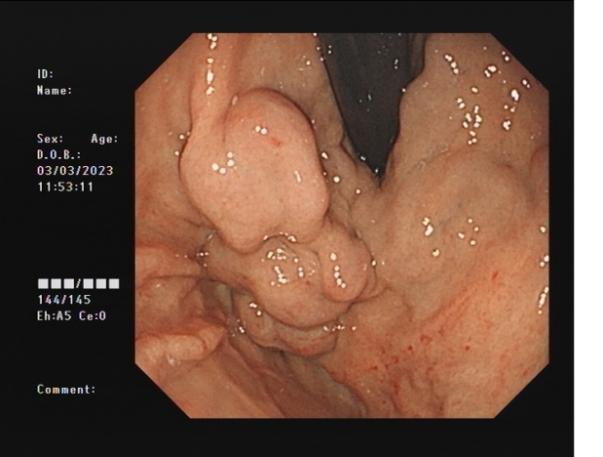

3b2d4fd666c540e5a8957f178dfb0b6b.Jpeg38cdda0ed1d245cfa077b1a308a229ca.Jpeg

內(nèi)痔                    內(nèi)鏡下內(nèi)痔硬化治療

內(nèi)鏡下內(nèi)痔硬化術(shù):治療I-Ⅲ度內(nèi)痔伴有內(nèi)痔相關(guān)癥狀;I~Ⅲ級(jí)內(nèi)痔飲食及藥物治療無(wú)效;內(nèi)痔手術(shù)后復(fù)發(fā),肛門反復(fù)手術(shù)后不能再次手術(shù);恐懼外科手術(shù),不愿意接受手術(shù)治療;高齡、高血壓、糖尿病和嚴(yán)重的系統(tǒng)性疾病,不能耐受外科手術(shù)等。